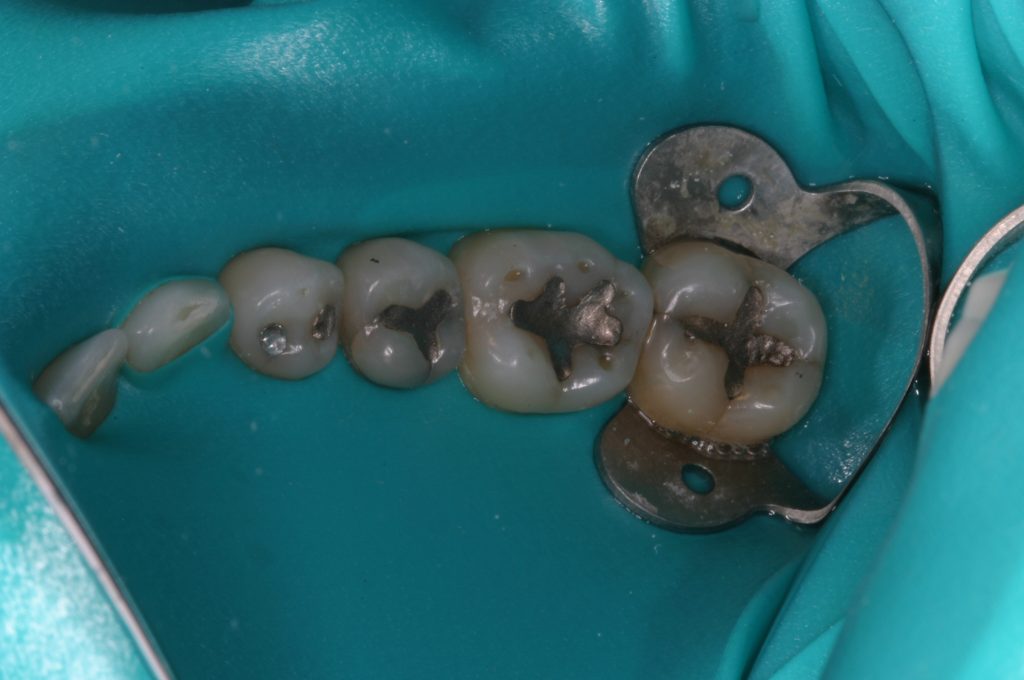

We are committed to creating a healthy environment for all of our patients. We are happy to discuss any or all of these topics with you and are committed to giving you all the information you need to make an informed healthcare choice. Dr Whicker is a member of the Holistic Dental Association and the International Association of Mercury Toxicology. We have all the equipment, materials, and protocols needed to safely remove mercury fillings.

- Mercury-Free Environment: Abstains from using mercury fillings, safeguarding you from potential toxic exposures and advocating for environmental conservation.